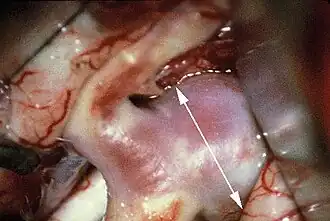

Es haben sich das Clipping und das Coiling bewährt. Die Methodenwahl hängt neben der Verfügbarkeit vor allem von den spezifischen Gegebenheiten des jeweiligen Aneurysmas (Erreichbarkeit, Form, Weite des Aneurysmahalses, Ursprung von Gefäßen) ab:

- Clipping (Verschluss durch eine Klemme) des Aneurysmas als neurochirurgischer Eingriff, um ein Nachbluten zu unterbinden

- Coiling des Aneurysmas als interventionelle radiologische Methode über einen intravasalen Katheter. Beim Coiling wird eine feine Platinspirale in den Aneurysmasack eingeführt. Damit werden Gerinnungsvorgänge initiiert, die über die Fibrinbildung und bindegewebige Umwandlung zu einer Verödung des Aneurysmas führen.

![]() |

Beide Methoden, Clipping oder Coiling, erfolgen für gewöhnlich in den ersten 72 Stunden nach Blutung oder erst 10 Tage später, da die Gefäße in der Zwischenzeit besonders empfindlich reagieren und die Entwicklung von Gefäßspasmen wahrscheinlich ist.

Die chirurgische Therapie ist mit hoher Evidenz zur Prophylaxe von Rezidivblutungen geeignet.[7]

Das Coiling bietet den Vorteil, dass man für den Patienten schonender zu den betroffenen Gefäßstellen vordringen kann, ohne dass, abhängig von der Lage des Aneurysmas, der Schädel eröffnet und Hirngewebe verletzt oder entfernt werden muss. Es ist auch zur Prophylaxe von asymptomatischen Aneurysmen geeignet.